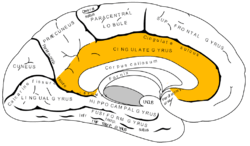

Medial surface of left cerebral hemisphere, with cingulate gyrus and cingulate sulcus highlighted.